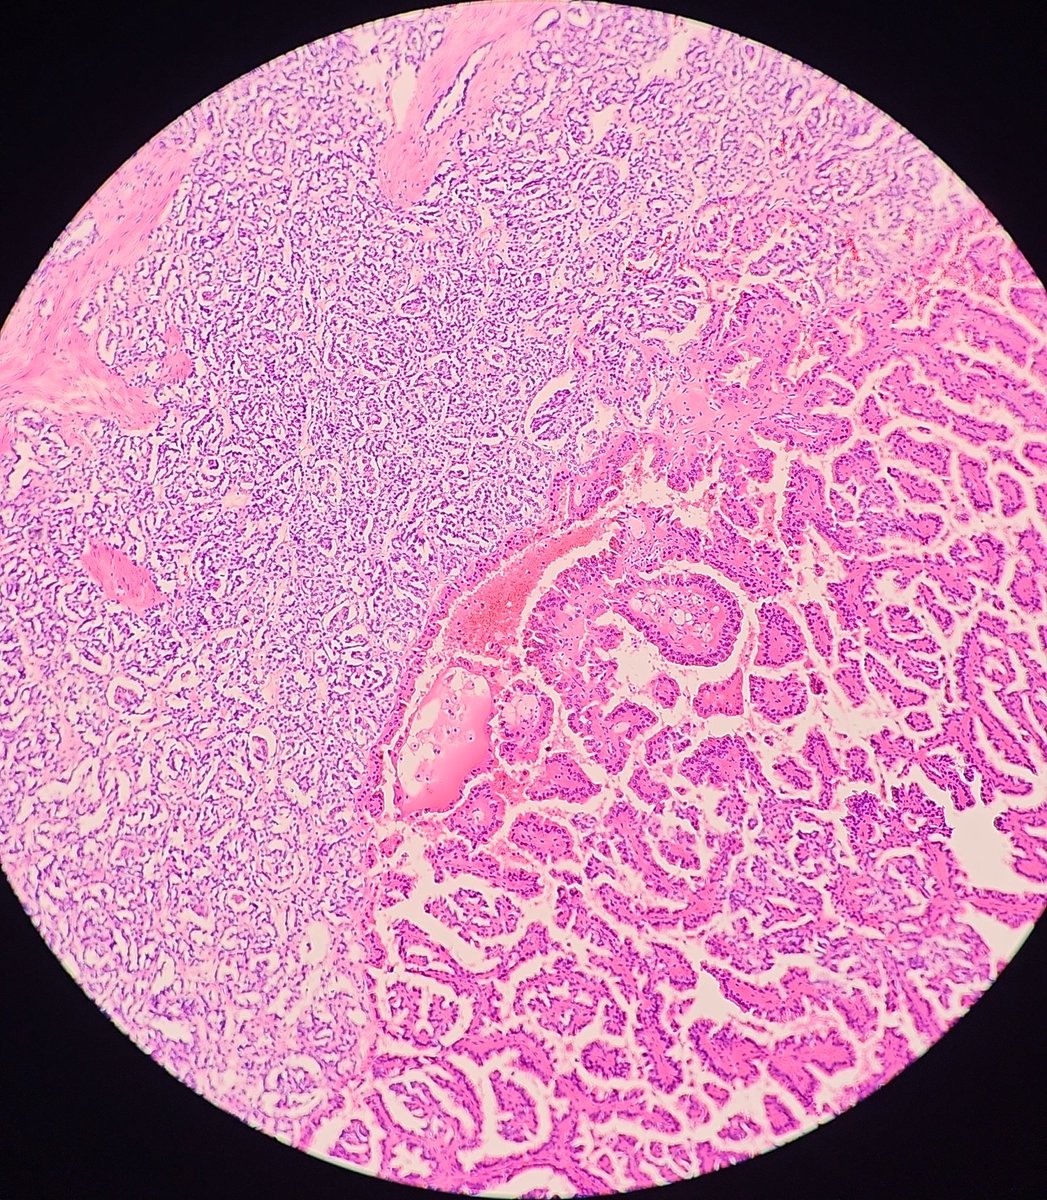

@JenyaMD

Papillary RCC showing type 1 and type 2 morphologies. #GUpath #pathology